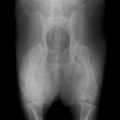

症例:右大腿骨遠位部の肉腫 クランバー・スパニエル 9歳 雌(未避妊)

2か月前から右後肢の完全挙上が認められ、消炎剤による内科治療で改善しないとのことで、他院から紹介来院した。

レントゲン検査

骨生検および病理組織検査

レントゲン検査所見から、骨もしくはその周囲組織に発生した腫瘍の可能性が考えられたため、病変部の細胞診検査およびジャムシディ生検針を用いた病変の骨生検を実施した。病理組織検査の結果、非上皮性の悪性腫瘍である“肉腫”と診断された。

内科治療に反応が乏しい四肢の跛行や疼痛は、本症例のように腫瘍が原因となっていることがあるため、レントゲン検査、骨生検等積極的に原因追及のための検査を実施することが必要である。骨の破壊を起こす悪性腫瘍は、非常に強い痛みを伴い、消炎鎮痛剤を用いても痛みを抑えることが困難となる。痛みの除去および腫瘍の治療のために断脚手術や抗がん剤等が必要となる場合があり、似た症状を示す整形外科疾患等とは治療法・予後が異なるため、その鑑別は重要である。